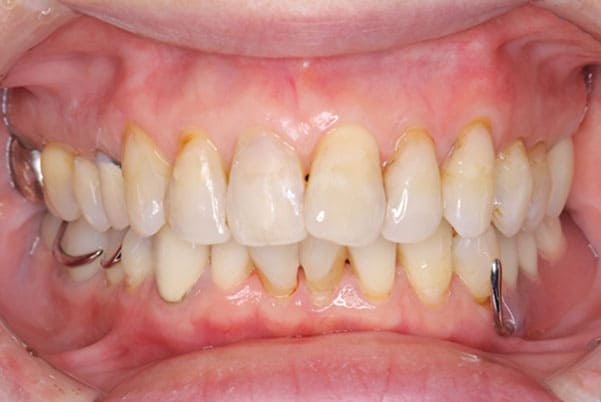

症例レポート[CASE.01]

義歯が合わず痛い、

見た目も気になる

- 性別・年齢

- 女性(40代)

- 主訴

- 下の義歯が合わず入れると痛みがある、見た目も気になるので外にはつけていかない

- 治療

- 下顎精密金属床部分入れ歯

- 治療期間

- 約2か月間

- 費用

- 55万円(税込)

入れ歯が沈み込むことを防止するストッパーがない入れ歯を装着されていたため、お食事により入れ歯が沈み込みお痛みがでている状態でした。

笑った際に、太いバネが左右に見えるため、あまり大きく笑うことを避けていらっしゃいました。

作製した入れ歯は、お食事の際に入れ歯の沈み込みを予防するため、適切なストッパーを付与することで、入れ歯は沈み込まなくなり、お痛みは消失しました。

右下のバネの位置は後ろに、左下のバネは見えづらい形態のバネを用いる設計とすることで笑った際にバネが見えないようになり、気にされることはなくなられました。

裏側の見えない部分は金属を用いることで、お食事の際の入れ歯の動き、沈み込みを抑えお痛みがでづらく、入れ歯の動きが抑制されることで、長期的に残りの歯に負担のかかりにくい設計としました。